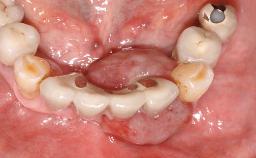

A 35-year old female patient was referred to the Department of Oral Surgery and Stomatology at the University of Bern, Switzerland, for examination of an implant site that had exhibited clinical signs of slightly delayed wound healing. In addition, the referring clinician found no evidence for a facial bone wall when she raised a flap to gain access to the implant for abutment connection. Four months earlier, she had inserted a bone-level implant in a single-tooth gap, where the lateral incisor had been extracted due to a chronic periapical lesion on the mesial aspect of the root. Implant placement was combined with simultaneous bone augmentation using deproteinized bovine bone mineral (DBBM, Bio-Oss®; Geistlich, Wolhusen, Switzerland) and a collagen membrane (Bio- Gide®; Geistlich), followed by primary wound closure. The patient also provided the postsurgical radiograph that displayed the implant with a 3.5-mm healing cap.

Case Type Single-Tooth Space

Jaw Maxilla

Area Anterior

# of Teeth 1

# of Implants 1